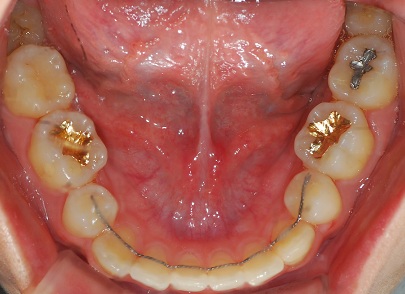

하악사진